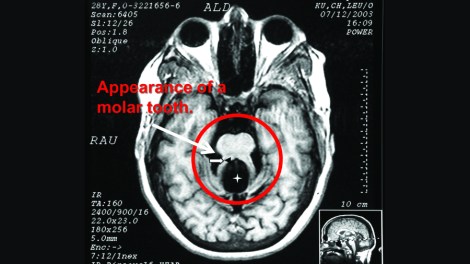

About 40% of people with Joubert Syndrome (JBTS) have autism. Most also have intellectual disability and experience developmental delays. The hallmark feature of JBTS can be seen on structural MRIs, in which the area around the midbrain and cerebellum gives the appearance of a molar tooth on x-ray. This is due to structural abnormalities within the midbrain, the white matter tracts leading to and from the cerebellum, and within the vermis of the cerebellum itself.

Above is the hallmark “molar tooth” seen in the MRI of someone with JBTS. Adapted and borrowed from here.